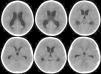

Teratoma is a common form of germ cell tumors composed of multiple tissues foreign to the site in which arise with a histological representation of all three germ cell layers. Intracranial teratomas are very rare. In this study, we report three cases of intracranial teratomas with an interesting clinical course, neuroradiology, and outcome. In addition, we review the literature and convey important messages to the neuroscience community regarding issues related to the management of these rare tumors. The present cases are interesting examples of intracranial teratoma in terms of location of the tumor and neuroimaging findings. Delay in surgical intervention may complicate the course of the disease with progressive enlargement of tumors and development of complication including hydrocephalus. Using endoscopic surgical techniques may emerge as the preferred intervention option as compared to other traditional methods. We recommend the establishment of a national and international registry for intracranial tumors.